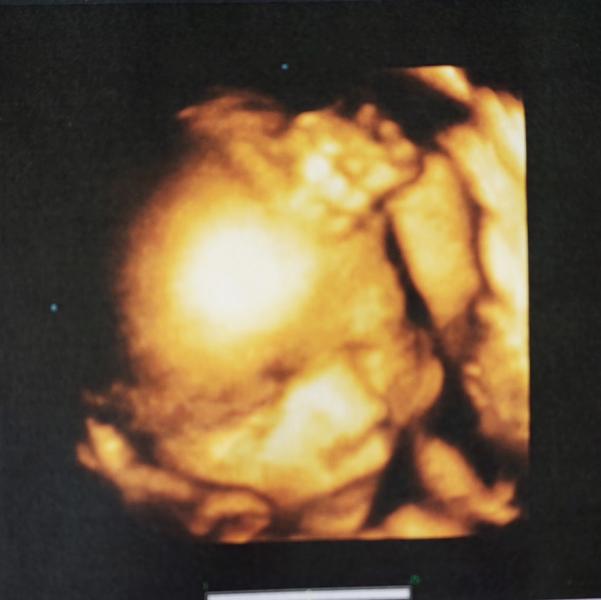

Вчера вечером ездили с мужем на УЗИ в #ЦИР к Тамаре Исаевне Нагоевой. Вот прям от всей души жалею, что в прошлый раз не к ней ходила - очень понравилась! Все показала, рассказала, объяснила и ответила на все вопросы. Внимательный и доброжелательный врач.

Наш мальчонка уже совсем большой! 36 см роста и 1385 гр веса))) и целых 6 см длина стопы (моя мама говорит, что мне в год (!) были велики туфельки 10,5 см) - прям мужичок растёт. Очень было интересно смотреть как с ...